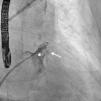

A 61-year-old man, with a history of coronary heart disease and percutaneous coronary intervention, with stents in the right coronary and circumflex arteries, was referred to our center for left atrial appendage (LAA) closure. He had atrial fibrillation with high thromboembolic risk (CHA2DS2VASc=4) and oral anticoagulation was formally contraindicated because of recurrent severe bleeding. Selective angiography of the LAA (Video 1) showed a close relationship between the LAA (Figure 1, asterisk) and the circumflex artery (Figure 1, arrow), well defined by the previously implanted stents. A computed tomography scan performed after a previous episode of diffuse alveolar hemorrhage showed similar findings (Figure 2, arrow). A 22-mm Amplatzer Amulet device was successfully placed, with no residual leak. Intraoperative monitoring by transesophageal echocardiography and post-procedural radioscopy confirmed the close relationship between the device and the circumflex artery (Figures 3 and 4, Videos 2 and 3), which is vital to keep in mind in order to prevent complications during the procedure.

After the Amplatzer was completely deployed, radioscopy confirmed the relationship between the distal lobe of the device and the coronary artery. Although in this patient this latter structure was easily delineated by the previously implanted stents, it is vital to consider this anatomical relationship during the occlusion procedure.